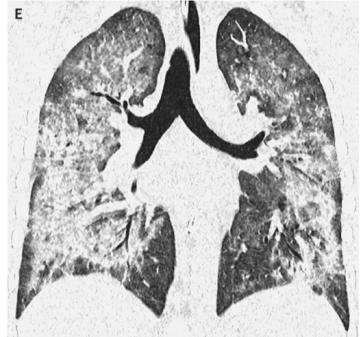

- 98%的患者出现呼吸道症状,81%出现胃肠道症状,100%出现全身症状。所有患者均有胸部成像双侧浸润(图1);

图1. 双肺浸润